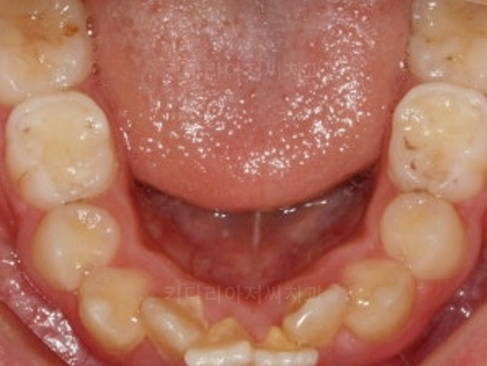

윗니와 아랫니 모두 매우 삐뚤한 것을 볼 수 있습니다.

특히 삐뚤함의 정도가 심한 부위는 양치질이 힘들기 때문에 치석, 플라그, 잇몸염증이 보였습니다.

나이에 비해 아직 치아 나이가 어려 유치도 존재하고 있었습니다. 조만간 영구치로 모두 전환이 될 것으로 예상되었습니다.